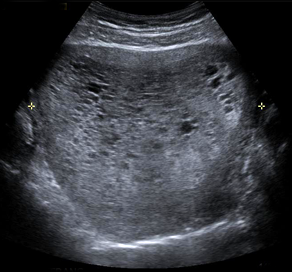

Molar Pregnancy